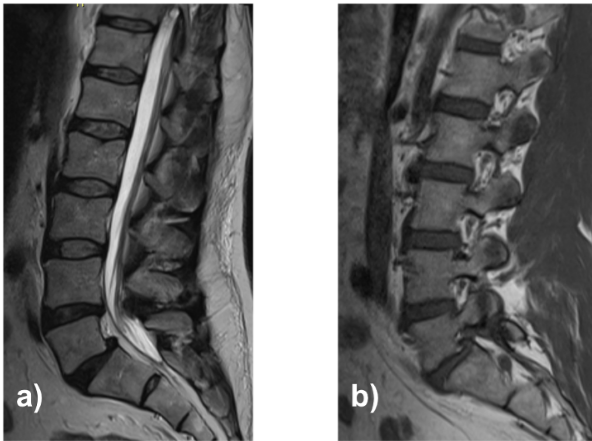

A 55-year-old male with a history of repeated corticosteroid exposure presented with a 3-month history of right-sided lumbosciatica, progressive paresthesias, and neurogenic claudication at approximately two blocks of ambulation. Magnetic resonance imaging demonstrated a grade I lytic spondylolisthesis at L5–S1 with severe foraminal stenosis and an L4–L5 disc herniation in the setting of a congenitally narrow canal (Fig. 1).

Figure 1: Lumbosacral magnetic resonance imaging: Sagittal T2-weighted (a) and right parasagittal T1-weighted (b).